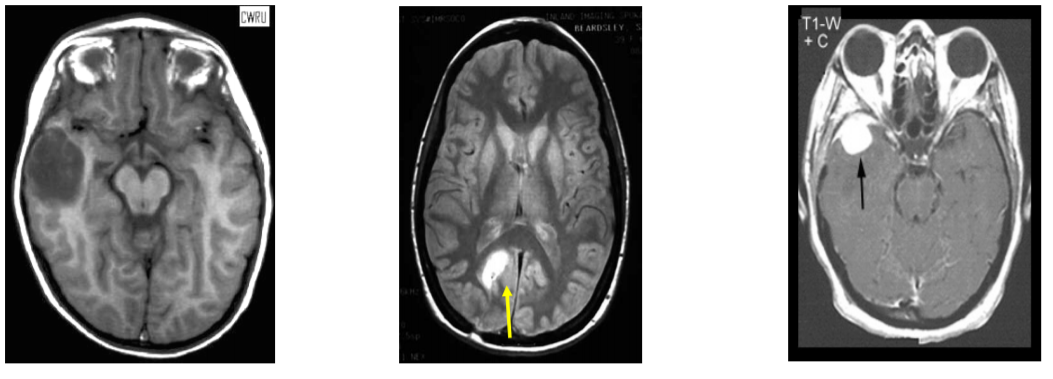

What can be seen in this scan?

[EXTRA? Possible MCQ]

What do these scans show?

(Pathology on left scan, right scan is an age-matched control)